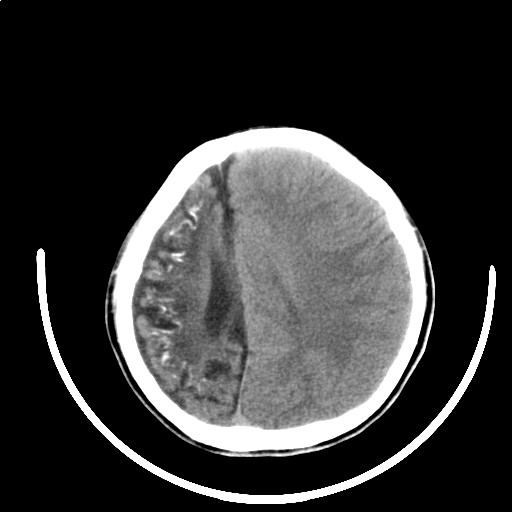

标题: PED3416:F,12Y,智力下降,学习成绩差,8个月时发过高烧。

不出意外的话,患者面部也应该有血管瘤的改变。符合颅颜面血管瘤的表现。

我仔细看过,患儿面部没有血管瘤改变。

右侧大脑发育不良伴动静脉畸形。

颅面血管瘤病(sws)。

右侧半球萎缩,软化,多量脑回样钙化,考虑颅面血管瘤病,建议dsa检查

右侧半球萎缩,软化,多量脑回样钙化,同侧颅盖板障增宽,考虑颅面血管瘤病,建议dsa检查与化脓性脑膜炎后遗改变鉴别。